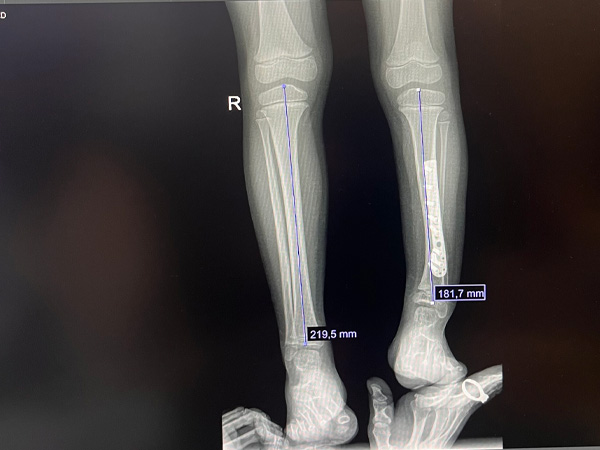

5-годишната Йоанна Вълчева е в ремисия след тежка и продължителна борба с ембрионален рабдомиосарком, но сега се налага да й се постави фиксатор (апарат на Илизаров) за удължаване на лявото ѝ краче.

„Към момента дължината на крачето изостава с около 4 см. Когато Йоана беше на 10 месеца, в България ѝ направиха операция за отстраняване на "киста" в лява тибия, а всъщност това е било туморно образувание. При извършването на интервенцията по невнимание или небрежност е бил прекъснат растежът на лявото краче“, разказва майката на детето Мария Вълчева.